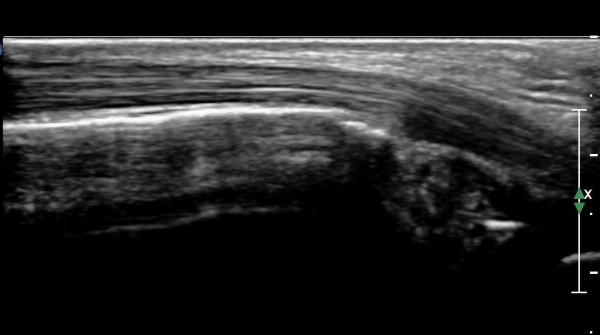

Á¾°ñºñ°ñÀδë Á¾´Ü¸é°Ë»ç¿¡¼­ °Å°ñÇϰüÀýÀÇ ¼ö¾×Àú·ù(Á¾°ñºñ°ñÀÎ´ë ½ÉºÎ ¼ö¾×Àú·ù)°¡

°üÂûµÈ´Ù(»çÁø 4).